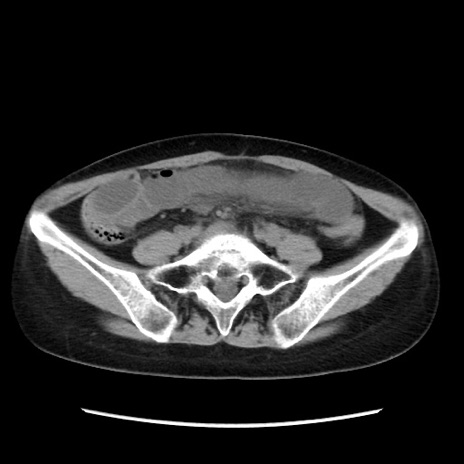

症例32(横断像)

【症例】40歳代 女性

【主訴】上腹部痛、嘔気・嘔吐

【現病歴】約9時間前頃から急に上腹部痛、嘔気、嘔吐が出現。改善しないため救急要請。

【既往歴】子宮頚癌(広汎子宮全摘術、放射線療法)、腸閉塞

【身体所見】腹部:平坦、軟、腸雑音亢進、上腹部を中心に腹部全体に圧痛あり。

【データ】WBC 8400、CRP 0.03